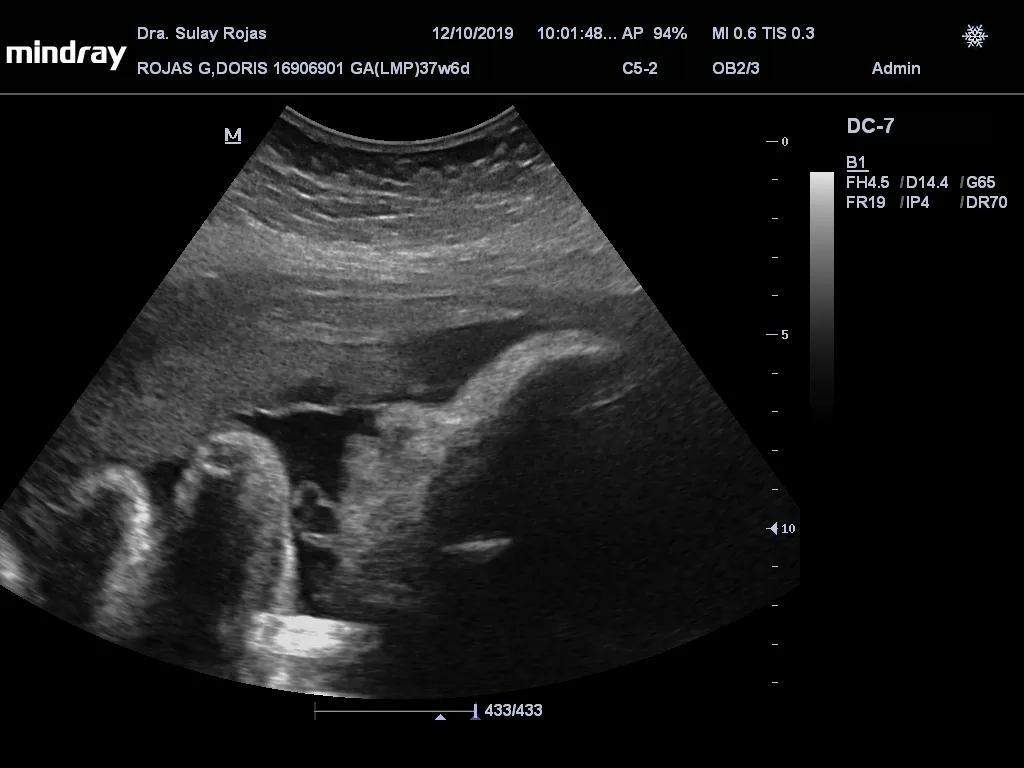

Algo que nunca olvidaré de mi embarazo, fue escuchar los latidos de su corazón, es algo tan hermoso y es muy difícil expresar con palabras como me hizo sentir esto, son dos vidas conectadas en un mismo cuerpo y tal vez, en el futuro él no recuerde mis latidos, pero sus primeros días de vida eran algo que lo hacían sentir seguro, pero yo siempre recordaré ese último ultrasonido y sí a veces extraño sus pataditas en la pancita.

Something I will never forget about my pregnancy was hearing the sound of his heartbeat, it is something so beautiful and it is very difficult to express in words how this made me feel, they are two lives connected in one body and maybe, in the future he will not remember my heartbeats, but his first days of life were something that made him feel safe, but I will always remember that last ultrasound and yes sometimes I miss his little kicks in the belly.